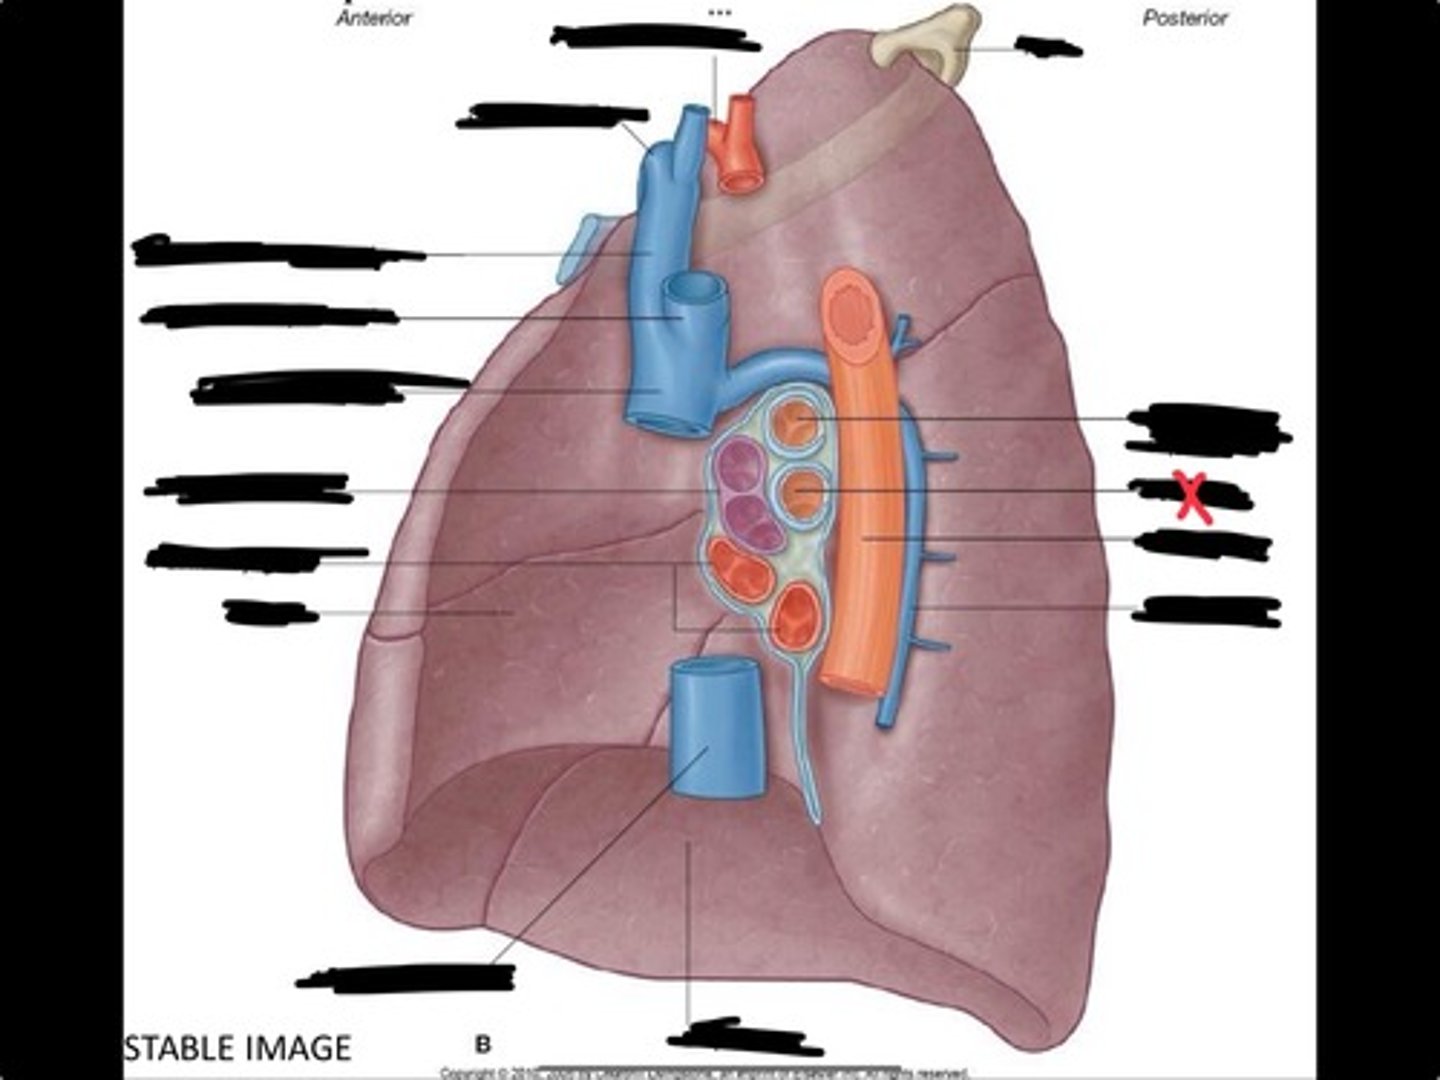

Lung

Pleural cavity

Visceral pleura

Parietal cavity

Esophagus

Bronchus

Pulmonary artery

Pulmonary vein